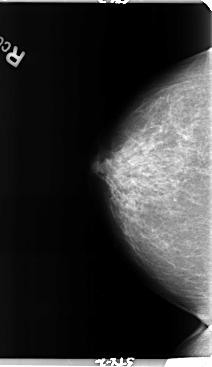

B_3158_1.RIGHT_CC

B_3158_1.LEFT_CC

LEFT_CC LINES 4760 PIXELS_PER_LINE 2976 BITS_PER_PIXEL 12 RESOLUTION 50 OVERLAY

RIGHT_CC LINES 4760 PIXELS_PER_LINE 2744 BITS_PER_PIXEL 12 RESOLUTION 50 NON_OVERLAY

FILE: B_3158_1.LEFT_CC.OVERLAY

TOTAL_ABNORMALITIES 1

ABNORMALITY 1

LESION_TYPE MASS SHAPE LOBULATED MARGINS CIRCUMSCRIBED

ASSESSMENT 3

SUBTLETY 3

PATHOLOGY BENIGN

TOTAL_OUTLINES 1

BOUNDARY